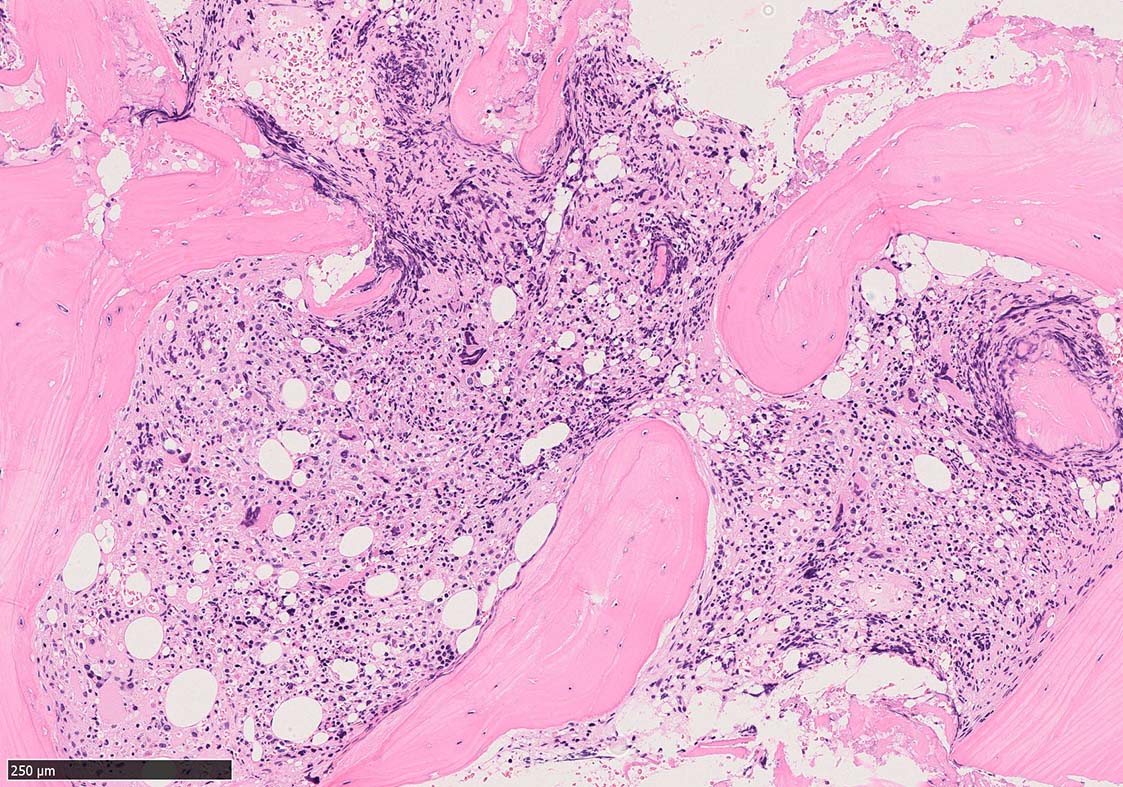

Case02; Meylofibrosis, overt fibrosis

77year-old female. 40歳時polycythemia veraと診断されていた.

[注] この症例は詳細は不明であるが, 過去にPVと診断されているため, PVに伴う二次性のmyelofibrosisの診断になる.

黒染する弾性線維の増生のほか, 赤く染まる膠原線維の増生が確認される. MF-2 fibrosis. 鍍銀染色の核染色をすると膠原線維の赤染がわからなくなるので行わない.